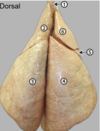

who does this kidney belong to?

cow